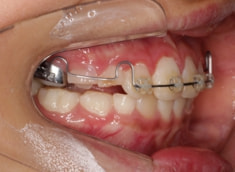

治療開始から6ヶ月後

治療法:上顎拡大装置+フルパッシブブラケット(クリアスナップ)+フェイスマスク等

治療開始から6ヶ月で反対咬合の解消は達成されておりますが、これで治ったわけではなく、上顎の劣成長を改善しなければならないので、ここからしっかりとフェイスマスクを使用していただきます。